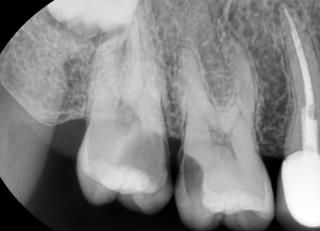

충치는 산성으로 인해서 치아의 구조가 무너지는 현상입니다.충치라고 무조건 치료를 하는것이 아닙니다. 충치도 종류가 있어요충치는 정지된 충치가 있고 진행되는 충치가 있습니다.우선 건강한 치아를 한번 볼께요 이 사진은 건강한 상태의 치아 입니다.이전에 레진 치료를 받은 흔적이 있지만 충치가 없는 상태의 치아에요.이 사진은 검은색으로 보이는 부위가 충치입니다.이 사진에도 치아를 따라서 보이는 검은 것이 충치에요.충치가 생겼을 때는 보시는 바와 같이 육안으로 확인할 수 있습니다.이렇게 검은색을 띠고 단단한 형태는 정지되어 있는 충치라고 볼수 있습니다.충치가 있는데 다시 석회화 되면서 충치가 더 진행이 되지 않는것이지요.이런 충치의 경우 충치니까 치료를 해야 하는것은 맞습니다. 하지만 진행이 되지 않고 정상적으로 기능을 하기 때문에 관리를 잘 한다면 치료를 보류해볼수 있어요.이 사진에도 충치가 보입니다. 치아는 외부는 검은식이지만 내부는 갈색을 보이는데 이런 형태의 충치는 진행이 되는 충치 입니다. 이런 식의 충치는 푸석푸석하며 치아의 구조가 약해져 있습니다.이런 진행중인 충치인경우에는 빠르게 치료를 해줘야 합니다.충치가 오래 진행이 되다보면 치아의 치질이 손상되게 됩니다.충치가 생긴 부위는 방사선 사진으로도 알수있는데요.우선 정상적인 치아를 한번 볼께요.왼쪽의 치아의 머리는 하얗게 생긴 정상적인 치아입니다.다음사진은 충치가 있는 사진인데요. 두개의 치아 사이에 검은 음영이 보이는데충치가 생겼을 때는 이렇게 방사선상에 음영으로 보이게 되요이 부분이 충치에 의해서 파괴된 부분입니다이 충치가 치아안의 신경까지 진행이 되지 않으면 신경치료를 안하고 간단하게 치료할 수 있는데충치가 신경까지 진행된 경우에는 통증을 느끼게 되고 염증이 생겨서 신경치료를 동반한 보철치료를 계획해야 합니다.충치는 신경에 도달하기 전까지는 통증이 없기 때문에 진행이 많이 되고 난 다음에 병원에서 뒤늦게 확인하는 경우가 많아요따라서 평소에 관리를 잘하고 이상이 없어도 치과에서 주기적으로 검사하는 것이 좋습니다.충치는 오랜기간에 걸쳐서 생기기 때문에 충분한 관심을 가지고 관리를 해주면 생기는 것을 방지 할수 있어요그럼 여러분의 구강내에 충치가 생기지 않도록 충분한 관심을 가지고 칫솔과 치실을 이용하여 꼼꼼하게 관리를 해주세요.여러분의 치아는 소중하니까요